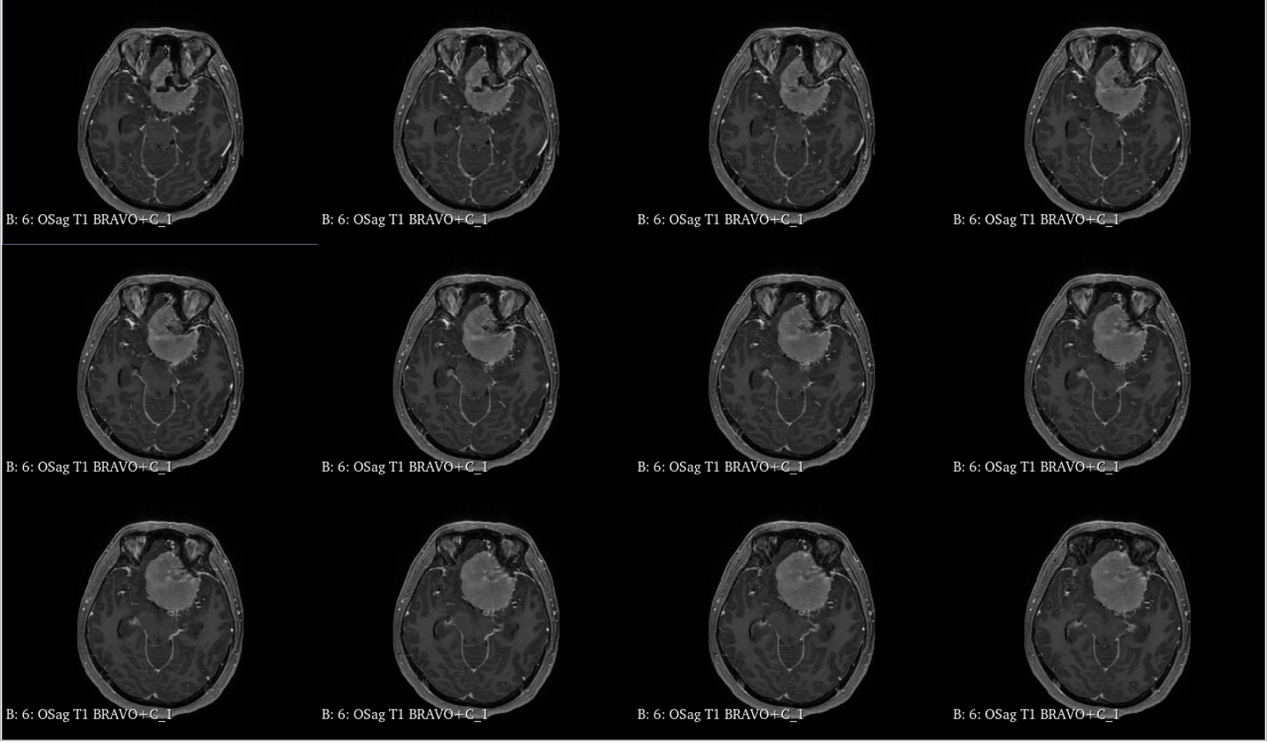

入院查体:神志清,精神可,言语流利,左侧瞳孔4mm>右侧瞳孔3.5mm,右侧对光反射存在,间接对光反射消失,左侧直接对光反射消失,间接对光反射存在,左眼失明,右侧鼻唇沟浅,四肢肌力及肌张力大致正常,双侧巴氏征未引出,颈软。

入院诊断:颅内占位病变(前颅窝底)脑膜瘤?;左眼失明;鼻炎

前颅窝底脑膜瘤常起源于前颅底筛骨筛板处的硬膜,瘤体多为双侧生长,少数为偏侧生长,女性稍多于男性。肿瘤可累及鸡冠和蝶骨平台的任何区域,是前颅窝肿瘤中最多见的一种。因为肿瘤位于前颅窝底,额叶在功能上属于“哑区”,患者就诊发现肿瘤时瘤体多已巨大。主要症状可有颅内压增高症状、视力减退、癫痫以及精神症状等。该患者主因“左眼失明10个月,头痛3个月”就诊。术中采用双额冠状开颅,左侧为主,由于肿瘤体积巨大,术中切除少许薄层额叶脑组织,边离断基底、边瘤内减压,分块切除肿瘤,最终探查肿瘤基底主要位于鸡冠、筛板、蝶骨平台、鞍结节、前床突处硬膜,术中见肿瘤供血主要来源于前颅窝底硬膜及大脑前动脉分支,术中仔细辨认供血动脉、过路血管,大脑前动脉及其分支保护完好,术中见视神经、视交叉受压明显,尤其是左侧视神经已缺血苍白,最终达Simpson II级切除。术者体会,该患者术前行多模态重建,可见瘤表数条粗大的静脉,术中切莫过早离断肿瘤的引流静脉,以防因引流不畅致瘤体肿胀出血;术前行多模态重建,利于鉴别供血动脉、过路血管,早期离断供血动脉更利于肿瘤切除;该类肿瘤基底一般较为广泛,不能盲目离断基底,尤其是近鞍结节处,可以于中线处离断基底,进入第一间隙后向两侧探查并保护视神经,待充分缩小瘤体看清楚毗邻的血管神经后再将其完全切除;术毕做好多层颅底重建以防脑脊液漏。另外,该患者术前左眼失明已达10个月,术后第1天即有光感,术后1月复查左眼视力可达50cm内数指,这在临床中非常少见,对于此类病人,不要轻易放弃挽救视力的任何机会。